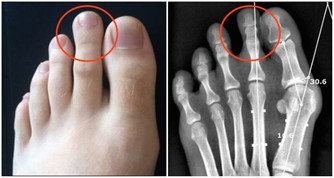

2.中老年人膝蓋疼是欠抽

在大會現場,《大河健康報》記者的左膝髕骨軟化,打過幾次封閉,至今上樓、爬山甚為不便。趙之心老師說:

「20多歲的年輕人就髕骨軟化?這是60歲以上的老人才會有的病。你給我靠牆罰站去。」

1保膝蓋靠罰站,打封閉不好使